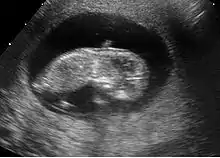

Fœtus à 10 semaines

Les caractéristiques humaines du fœtus sont évidentes. Les membres sont visibles. Le pied prend une angulation normale par rapport à la jambe. L'ossification du crâne commence par l'os occipital. Les repères principaux du cerveau sont visibles. La hernie physiologique des intestins à travers la paroi abdominale est à son maximum. L'estomac devient visible.